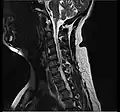

L'imagerie par résonance magnétique peut montrer la hernie, le canal vertébral, les nerfs, les tissus environnants. Les tissus mous sont les mieux analysés par cet examen qui est le plus performant pour le diagnostic de hernie discale. Les images pondérées en T2 montrent clairement la hernie.

IRM cervicale sagittale montrant une hernie discale de niveau C6-C7.